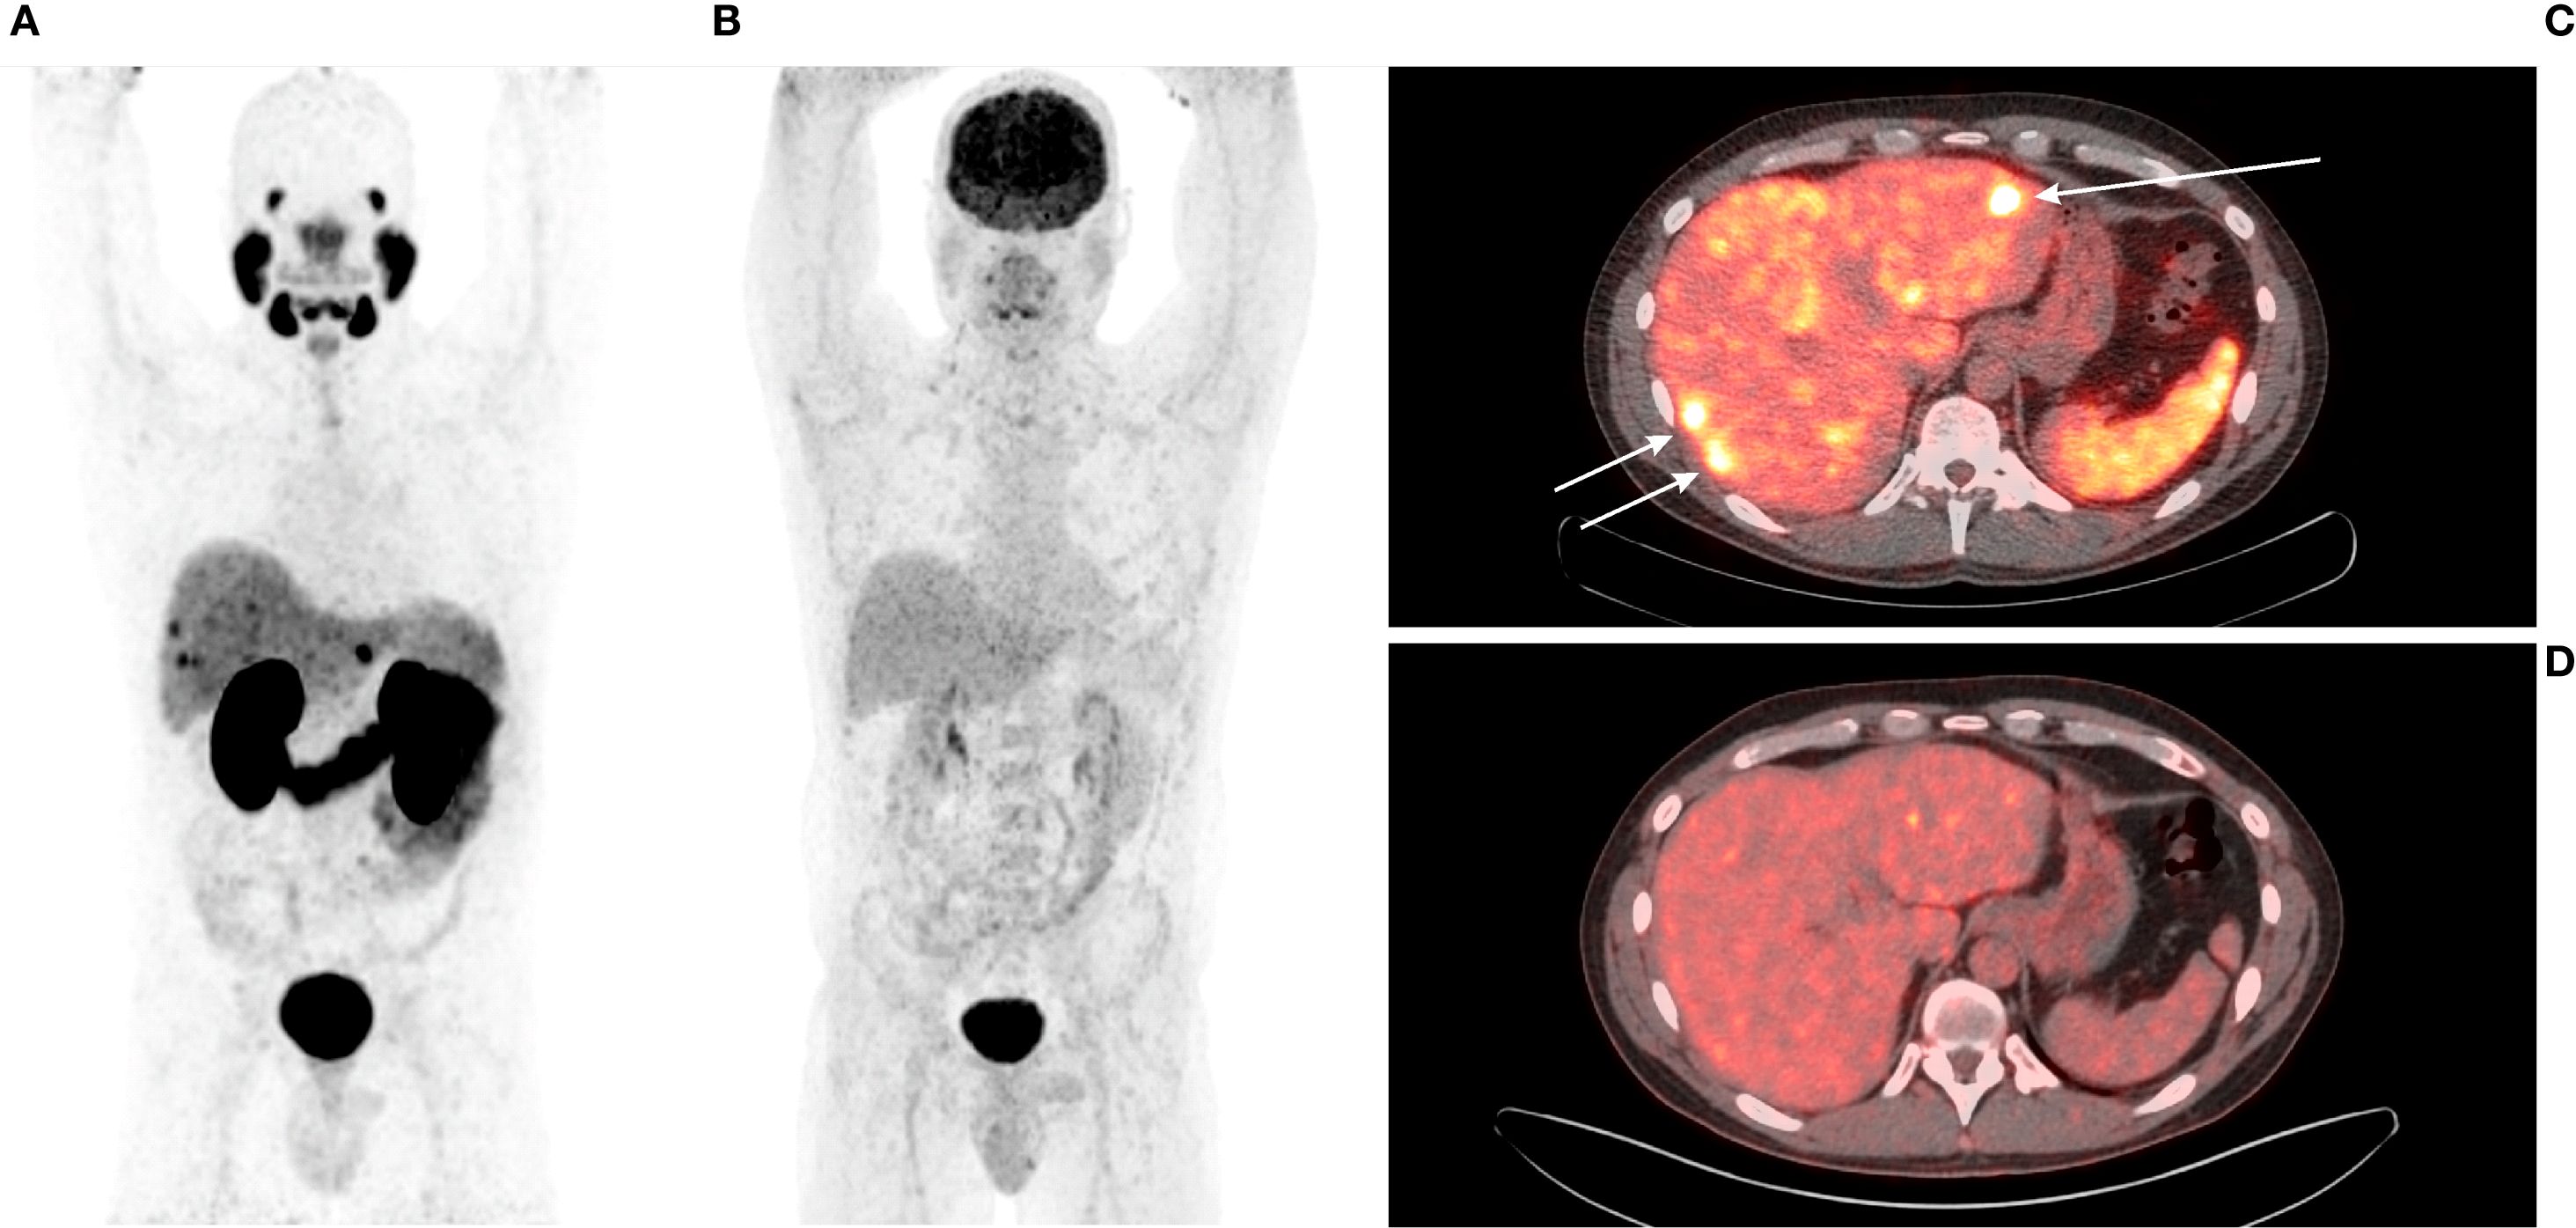

[68Ga]Ga-PSMA-11 PET/CT was positive in 5/12 patients – 3/3 patients with previously-identified structural lesions (a superior mediastinal mass, a metastatic cervical lymph node, and liver metastases; Figures 3–5) and 2/9 patients without previously known structural lesions. In both of these cases, [68Ga]Ga-PSMA-11 PET/CT revealed small lesions in the thyroidectomy bed, which could correspond to local recurrence or lymph nodes (one shown in Figure 6). The mean SUVmax, TBRBlood and TBRLiver values for detected lesions were 7.08 (range 2.74–12.37), 6.08 (range 3.19–9.82), and 2.23 (range 0.90–3.77), respectively.

Figure 5. (A) 42-year-old male with medullary thyroid carcinoma and liver metastases. (A) [68Ga]Ga-PSMA-11 PET MIP. (B) [18F]FDG PET MIP. (C) Transaxial view of the fused [68Ga]Ga-PSMA-11 PET/CT scan (white arrows). (D) Transaxial view of the fused [18F]FDG PET/CT scan. Liver metastases are avid on [68Ga]Ga-PSMA-11 PET (mean SUVmax 9.25; mean TBRLiver 2.82) and not avid on [18F]FDG PET (mean SUVmax 3.85; mean TBRLiver 1.61). All metastases were undetectable on non-contrast CT (not shown in the Figure).